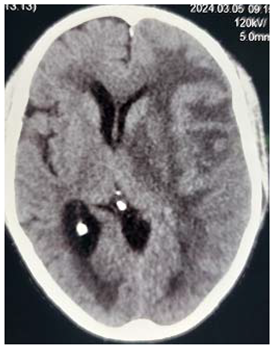

#Case 3:

This is 50 years male, empolayer, heavy smoker, presented to neurosurgery emergency unit with history of rabidly progressing headache, unsteady gait and deterioration level of consciousness for few months duration.

On examination: obese, his GCS was 14/15, moving his limbs adequately but irritable.

Consequent to resuscitation, and clear counseling to the family, the patient prepared for surgical decompression.

Operation: through Rt par median sub occipital craniectomy, macroscopic excision of the tumor was done. The tumor was lobulated well circumscribed, less vascular and extending to the cistern magna.

Patient showed good recovery after the completion of surgery, taken to the ICU on nasal oxygen, and 48 hours released to the general word.

Histopathology

Revealed brain tuberclomata ( extra pulmonary tuberculosis)

Patient was put on anti-tuberculosis according to the program.

In the 7th day post operative, the patient developed high grade fever with respiratory distress, the diagnosis of pneumonia was made and eventually intravenous antibiotic was given, unfortunately, 3 days following he developed Rt lower limb cellulites that complicated with shortness of breath and emergency intubation was done and put on mechanical ventilation but few hours following he died.